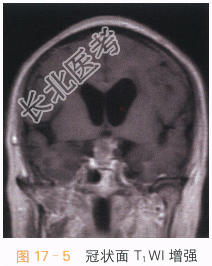

读片分析:头颅CT平扫见鞍上异常软组织影,并可见多发钙化,局部见“蛋壳样钙化”,横断面T₁W见鞍上异常软组织信号灶,呈等高信号影,T₂WI见病灶表现为囊实性肿块;增强扫描实性部分可见明显强化,囊性部分未见明显强化,但正常垂体结构能显示。结合患者临床,可考虑颅咽管瘤。